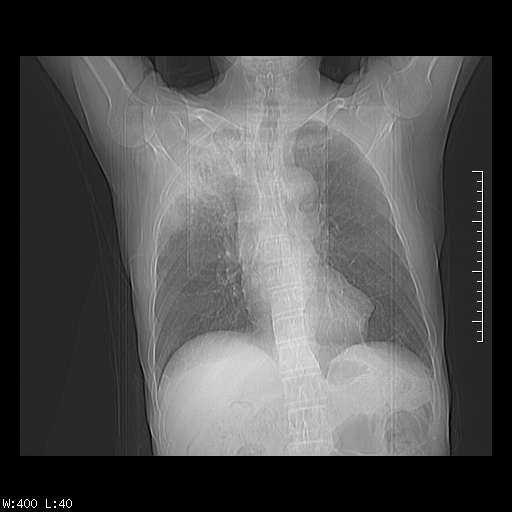

标题: CT23994:男、72、咳嗽、气短两月余,近来消瘦。 [打印本页]

标题: CT23994:男、72、咳嗽、气短两月余,近来消瘦。

右上肺实变,与胸膜关系密切,右肺容积缩小,隆突下淋巴结增大,考虑1 肺结核 2 肺癌

右上肺大片状密度增高影,与胸膜关系密切,内见低密度透亮影,胸膜下可见三角形不张影,左下肺沿支气管走形结节影,纵膈内淋巴结显示。考虑结核并疤痕性不张可能性大,建议穿刺活检,排除肺泡癌。